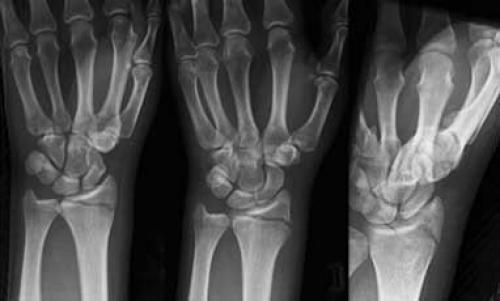

Рис. 2 а,б. На рентгенограммах разные типы перелом шиловидного отростка и дистального отдела лучевой кости.

Рис.3 а. схематическое изображение перелома Коллеса и Смита; б. на рентгенограммах перелом диафиза лучевой и локтевой кости в с/3 со смещением.